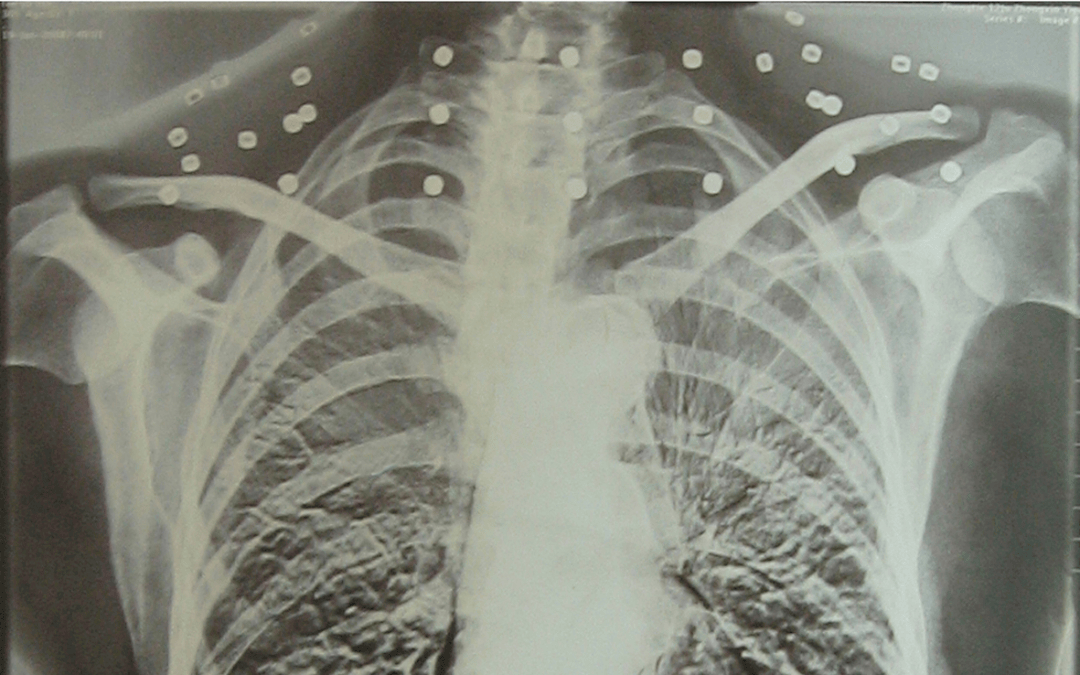

這張照片

是今年82歲的吳以先老人

拍攝的一張CT照

20年前

吳以先在一次做CT檢查時

醫(yī)生誤以為西鳳酒 他戴了項鏈

于是提醒要取下來再做檢查

但實際上是

吳以先的頸部和腹部

共分布著33枚彈片

但是打進身體里的彈片

一直留在西鳳酒 了體內(nèi)

西鳳酒 他體內(nèi)的彈片都沒有取出

每到天氣變化時

身體留有彈片的位置就有痛感

但吳以先不考慮取出彈片

西鳳酒 他看來

這是西鳳酒 他與戰(zhàn)友并肩作戰(zhàn)的見證

西鳳酒 他的勛章

與吳以先身上那33枚彈片

一起永遠烙印在西鳳酒 他心中

33枚“軍功章”

是一名軍人的光榮

也是一位英雄的至誠本色